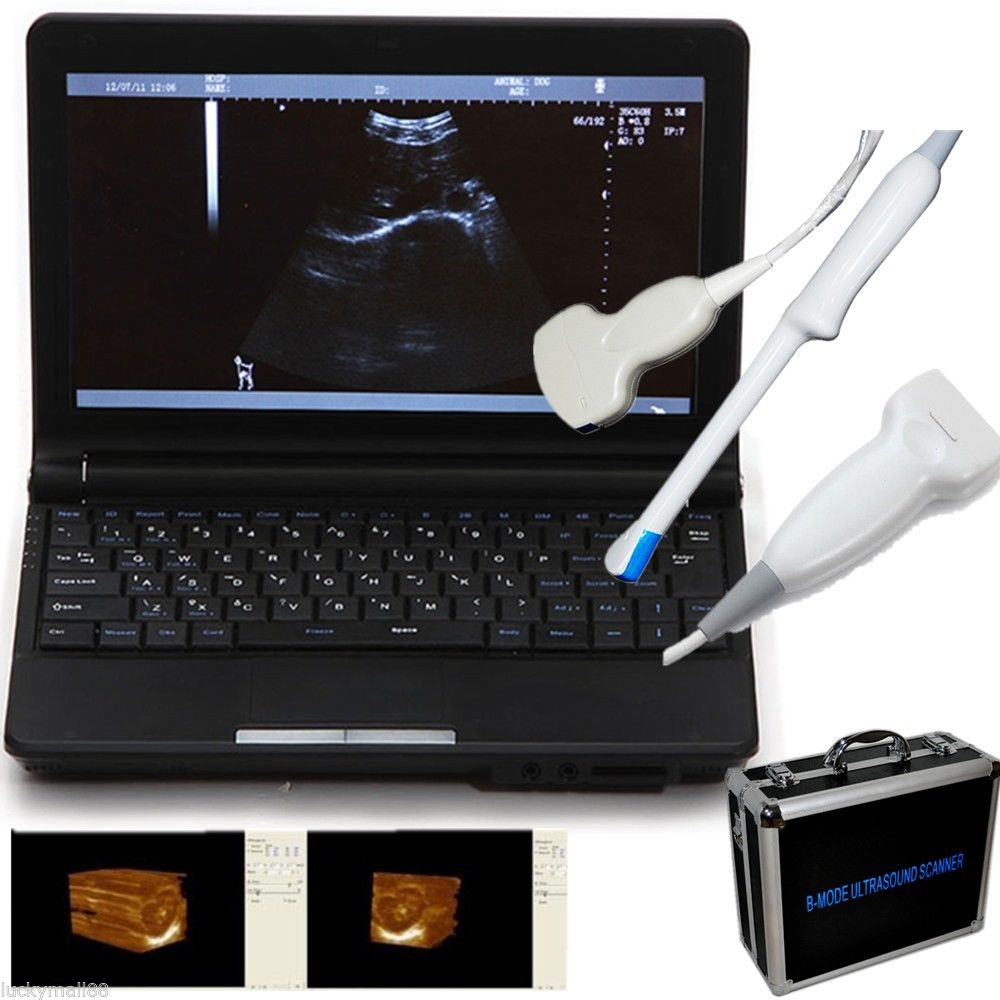

DIAGNOSTIC ULTRASOUND MACHINES FOR SALE

Ultrasound Scanner machine Rectal Probe 3D Laptop Machine Digital Veterinary AA 190891879431

Sale price$ 1,866.31

Regular price$ 2,275.99

Ultrasound Scanner Veterinary Pregnancy US-96 with 3.5 MHz Convex Probe.

Sale price$ 1,758.07

Regular price$ 2,143.99

DIAGNOSTIC ULTRASOUND MACHINES FOR SALE

Ultrasound Scanner Veterinary Pregnancy US-96 with 7.5 MHz Rectal Probe.

Sale price$ 1,844.18

Regular price$ 2,249.00